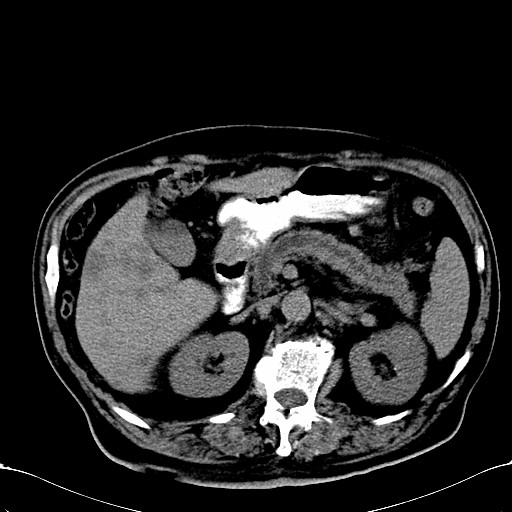

标题: CT28270:胰管扩张,肝多发占位 [打印本页]

标题: CT28270:胰管扩张,肝多发占位

患者,男,75岁。

考虑胰腺钩突癌并肝内转移,建议强化明确。

1)考虑胰头癌并肝脏多发性转移;建议行ct增强扫描检查。2)胃窦癌?建议行胃镜检查。

胰管有扩张,位置比较低,同意楼上几位高手意见。肝内转移可能大,建议增强。

肝脏多方低密度结节,边缘模糊,考虑多发转移,胰管明显扩张,建议增强扫描钩突情况

肝脏多发低密度灶,胰头似呈低密度,胰管扩张,建议增强,

胰管显著扩张,但胆总管未见扩张征象,不太符合胰头占位!考虑慢性胰腺炎.胃窦占位并肝内转移可能!mrcp胃镜增强一起上!